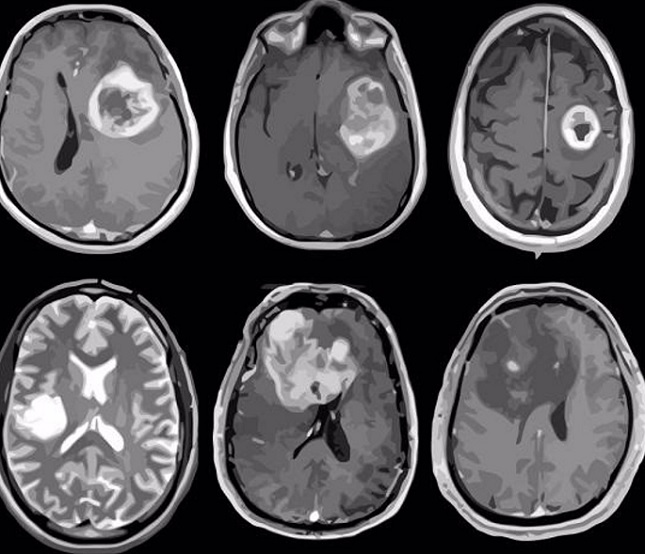

Cada año se diagnostican en España más de 5.000 nuevos casos de tumores cerebrales, que suponen aproximadamente el 2 por ciento de todos los cánceres diagnosticados en adultos y el 15 por ciento de los diagnosticados en niños, según datos de la Sociedad Española de Neurología (SEN).

Desde la SEN, con motivo de la celebración este jueves de su Día Internacional, advierten de que, este tipo de tumores que aglutinan más de 120 tipos en el sistema nervioso, en los últimos años se ha observado un incremento en el número de casos por año debido, principalmente, a la mejora de las técnicas de imagen -lo que ha permitido perfeccionar su diagnóstico-, y al progresivo envejecimiento de la población.

Se estima que, en la actualidad, en España hay alrededor de 20.000 personas que padecen algún tipo de tumor cerebral, clasificado bien como un tumor primario (originado en el cerebro) o como un tumor metastásico (originado en otras partes del cuerpo, pero que se ha diseminado al cerebro).

Los tumores cerebrales suponen aproximadamente el 2% de todos los cánceres diagnosticados en adultos y el 15% de los diagnosticados en niños, lo que le convierte, durante la edad pediátrica, en el segundo tipo de cáncer más detectado después de la leucemia. En todo caso, aunque no son los tumores más frecuentes, tienen un alto impacto en la vida de las personas que los padecen.